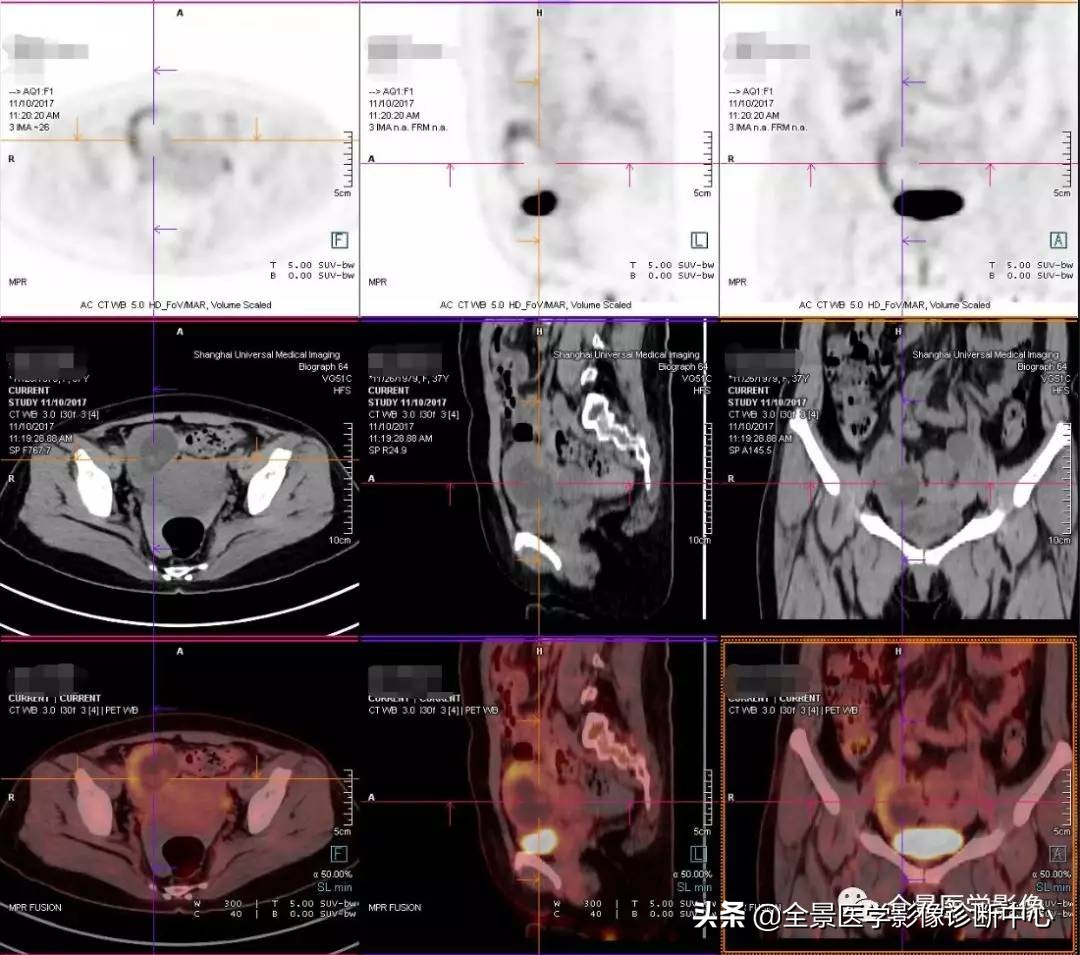

全景PET/CT诊断组李医生在开始为她进行阅片中发现其右侧附件区长了一个长径约8cm的囊实性奇怪病灶,病灶呈椭圆形,与脑海中浮现的所有附件常见病灶都不太相像。

即请全景医学影像石华铮主任会诊,坐定没一会儿,石主任倒吸了一口凉气说:这是发生于右侧输卵管的宫外孕呀,更为严峻的是:病人的宫外孕已经破裂伴有活动性出血(盆腔内子宫直肠陷凹出现较多游离高密度液体影)

也就是说检查者的腹腔内正在持续出血而自己竟然还不知情……遂立刻启动全景危急重病患处理预案,并为慎重起见,马上让杨春山教授再次复核影像诊断结果并获得支持,报备医务处,填报危急值表。